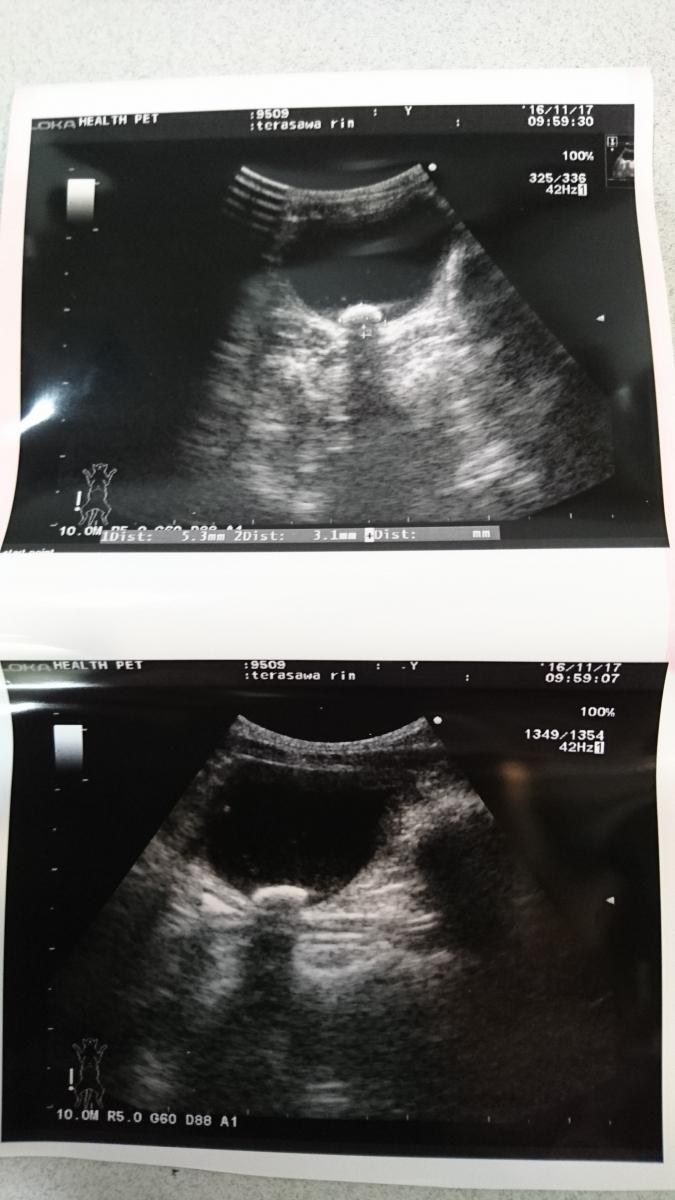

今朝一番でクリニックへ。今日は尿検査と超音波をしました。

膀胱炎の数値は悪くはない(少しだけ細菌がある=抗生物質で対応)が、、、結果結石ができてしまってました。5×3mmの大きさでした。もう自力では出ないとのこと。

白く丸いのが結石

いつから?もっと早く見つけらなかった?なんで?やはりストルバイトだ、、、💧💧、、どっといろんな事が頭を駆け巡りました。

りんはまだまだ小さすぎるので手術は「今は」できない、今後は目の前の治療をきちんとしていき、結石は経過観察して、大きくなったり、小さくならないようなら、、りんが成長した段階で手術。

小さくなることもなくはないとのことで、、大きくならないようにしていく。

そして圧迫排尿の仕方、回数、水をのませることなどなどいろいろきいてきました。座ってる状態なら結石は膀胱の下にあるから、斜め上からゆっくり圧迫排尿させる!と。